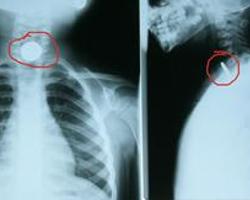

食管异物常发生于幼童及老人缺牙者,常因口中含物玩耍、饮食过快、囫囵吞咽、老人假牙咀嚼时感觉不灵敏,或睡熟时松动的假牙脱落而误咽形成食管异物。[1]